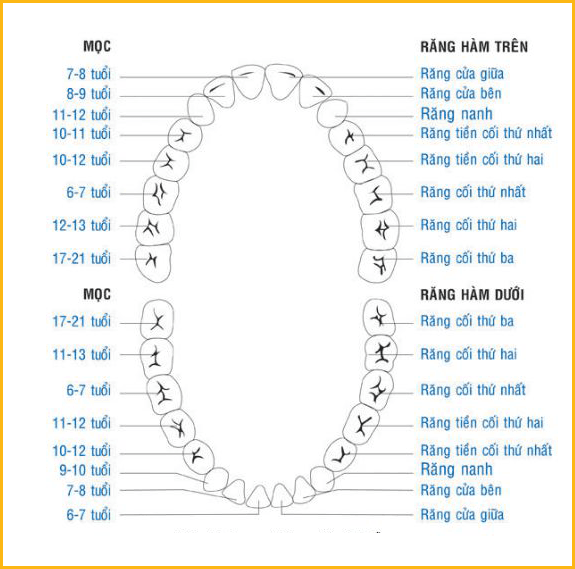

MỌC RĂNG VĨNH VIỄN